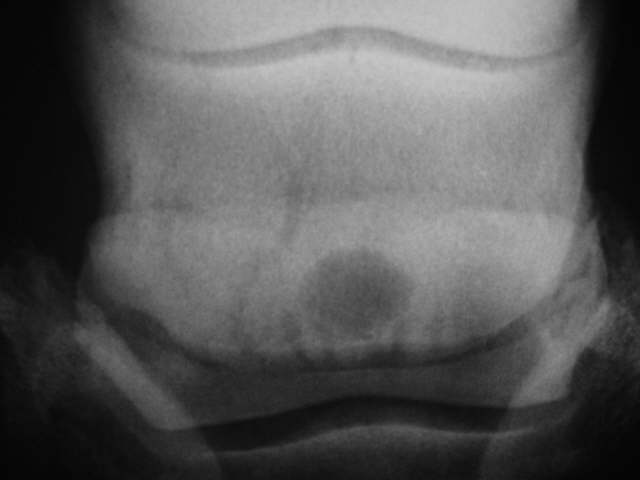

Sehr großer zystoider, zentraler Defekt und tief in das Strahlbein hinein ausgeprägte Gefäßkanäle. Röntgenklasse IV